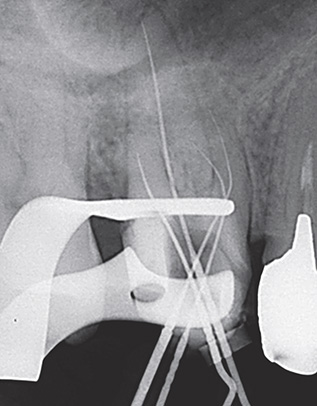

症例3-2 近心根の作業長測定。

症例3-3 遠心根と口蓋根の作業長測定。

症例3-4 再度、口蓋根の作業長を測定した。

症例3-5 根管充填後。